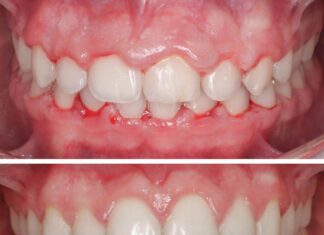

Hiperplasia o agrandamiento gingival